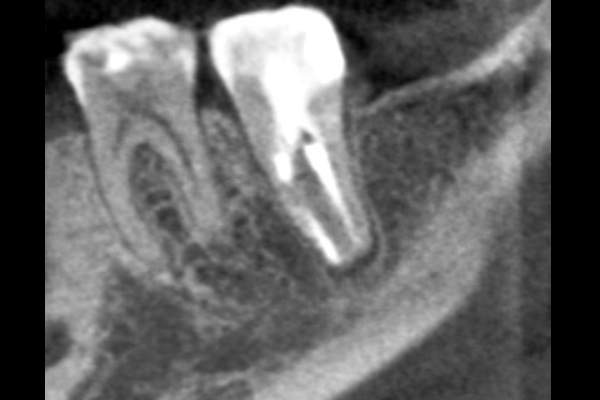

歯科用CTとは、エックス線検査では得られない情報を得るための、より精度の高い検査です。

歯科治療にマイクロスコープが必須になってきたように、今までエックス線検査で行っていた画像診断もまた、CTによる検査が必須になりました。 エックス線検査では観察対象を外側から見た際の影絵の濃淡で診断をしていましたが、CTは観察対象を任意の断面で切り取って観察する事ができ、いままでエックス線検査を元に、想像で補うしかできなかった部分を、鮮明な画像とともにその実際を教えてくれるのです。

今まではマイクロスコープがあったとしても、先を想像しながら根の先へ器具を進めていたのが、術前にCT撮影をしておくことで、あらかじめ3次元的な歯の形を認識した上で余計な部分を削らずに、器具を進められるようになります。

マイクロスコープと同様に歯科用CTについても、撮影すれば治療がうまくいくものではありません。撮影したデータを正確に読み取るための正しい知識と、訓練が必要になります。